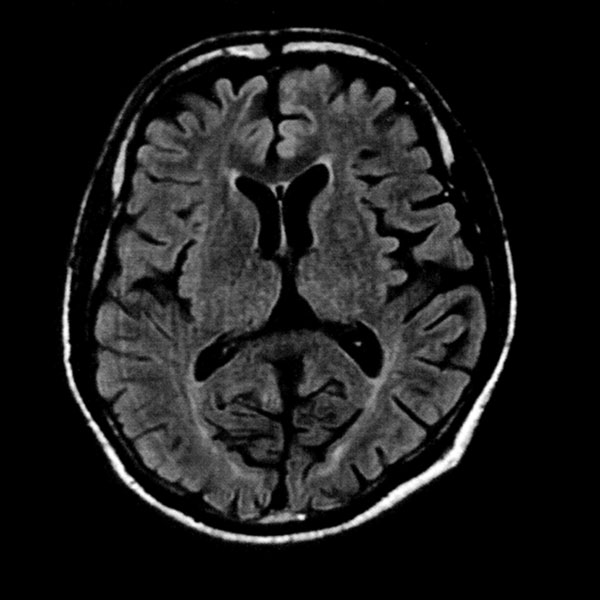

MRI検査

2025年9月16日スタート!!1.5T MRI SIGNA Creator(GE社製)

新しいMRI装置では従来の装置と比較し、高画質、かつ短時間での検査が可能となります。

- AI 機能を搭載:従来の装置と比べかなりの高画質が期待できます

- 従来の装置では難しかった微細な変化の描出にも期待がもてます

- PROPEELR 機能により、動きを抑えたきれいな画像が得られます